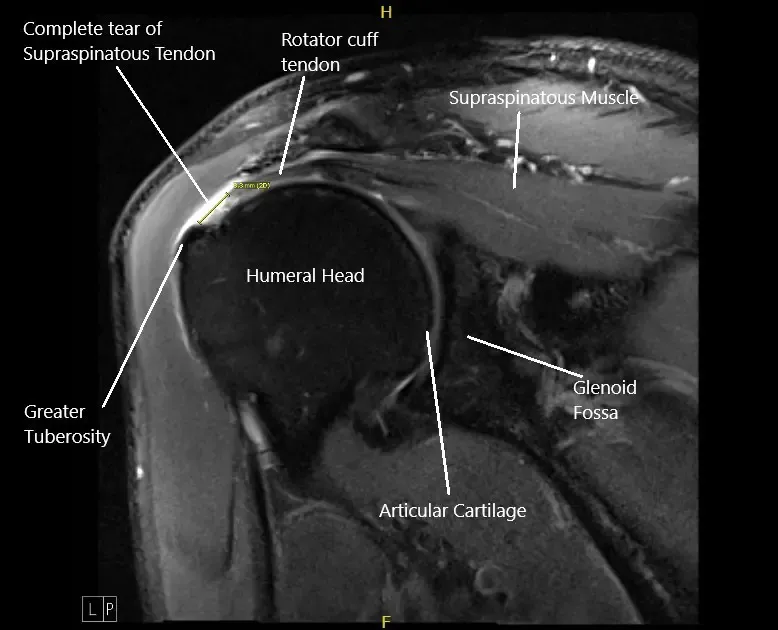

Imagen de resonancia magnética del hombro izquierdo mostrando una rotura completa del manguito rotador.

Los estudios radiológicos del hombro izquierdo sugirieron una rotura completa del tendón supraespinoso con 8 mm de retracción medial, tendinosis del bíceps de la cabeza y de la cabeza larga, bursis subacromial/subdeltoides y subcoracoidea, artrosis AC y degeneración del labrum posterior superior superior.